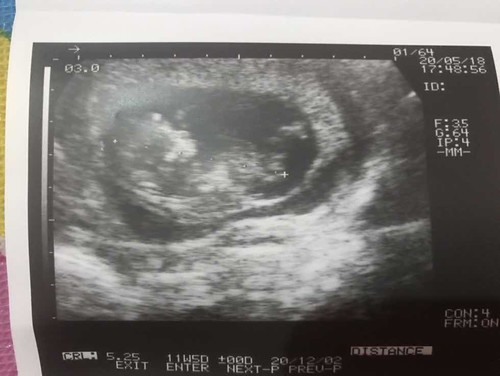

ตอนนี้ท้องได้ 10 สัปดาห์แล้วคะ ท้องแรก วันนี้รุ้สึกปวดท้องหน่วงๆเลยไปให้คุณหมอซาวน์ดู แต่ไม่ใช่คลีนิคที่ฝากครรภ์ เพราะคลีนิคที่ฝากหมอมาทุ่มนึงและคนเยอะมากต้องรอคิว ผลปรากฏว่าคลีนิคที่มาตรวจหมอพบการตั้งครรภ์ 2 ถุง ถุงนึงคือถุงเด็กกำลังโตหมอนับได้ 11 สัปดาห์ ตัวโต มีการดิ้นดุ้กดิ้ก มือขาขยับ หัวใจเต้น อีกถุงคือมองเห็นแค่เป็นก้อน มองไม่ชัดว่าเป็นตัวเด็กหรือแค่ถุงน้ำ แต่ไม่มีการเต้นของหัวใจ คุณหมอบอกใข่อาจจะฝ่อใบนึง ให้มาซาวน์ดูอีก 2 อาทิตย์ อยากทราบว่าต้องรอให้หลุดออกมาเอง หากปล่อยคนที่กำลังโตจะเป็นอันตรายไหมคะ จะหลุดออกมาด้วยมั้ย รุ้สึกกังวัลมากค่ะ